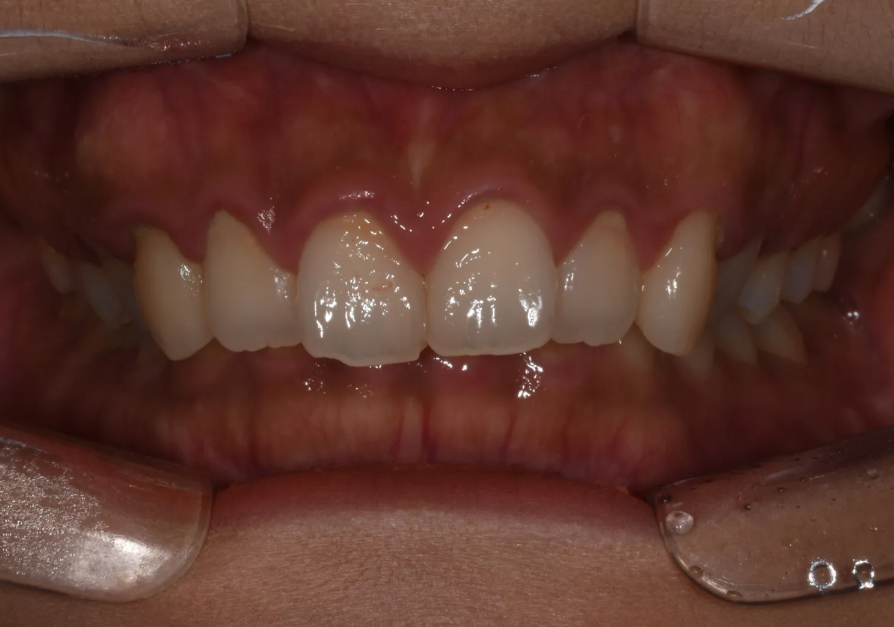

비수술 과개교합 교정 전후

'토끼이빨'이 고민인 20대 여자 환자

이 환자분은 20대 여성으로, "토끼이빨을 고치고 싶다"는 이유로 내원하셨습니다. 웃을 때 앞니가 과도하게 보이고, 잇몸까지 많이 드러나는 이른바 '거미 스마일(gummy smile)'이 심한 상태였습니다.

초진 시 구내 정면 모습. 끝까지 다물면 아랫니가 다 가려지는 심한 과개교합.

환자분께서 직접 "이~" 하고 보여주셨을 때, 과개교합의 정도가 정말 심해서 저도 놀랐던 기억이 있습니다. 이미 다른 치과에서 수술 교정을 권유받으셨지만, 수술이 부담스러워 치료 자체를 포기하려 하셨던 상황이었습니다.

하지만 정밀 진단 결과, 양이 많을 뿐이지 메커니즘 자체는 경도 과개교합과 다를 것이 없다고 판단했습니다. 따라서 비수술로도 충분히 개선 가능하다고 설명드리고, 교정 치료를 시작하게 되었습니다.